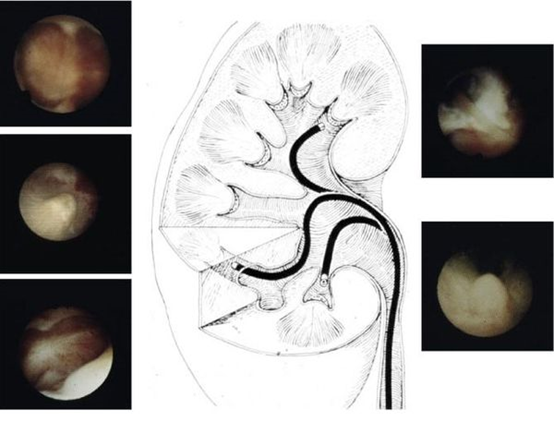

输尿管软镜操作演示

随着科技进步和技术革新,特别是国内2010年以来,输尿管软镜+钬激光碎石技术在泌尿系结石微创治疗方式上所占的比例越来越高,已成为治疗上尿路结石的一种重要术式。它本身可在肾内拐弯,镜体末端拐弯角度可达180°到275°,利用人体自然腔道,更加微创,可以同时处理输尿管上段和肾内结石,目前是2cm以下肾结石的主要处理方法,但也有许多2cm以上结石通过输尿管软镜碎石成功的病例。